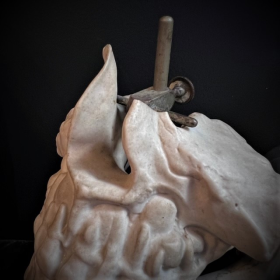

What is original is that the whole piece is made of unglazed porcelain, which is called biscuit, except for the teeth which are well glazed.

Original metal fixation system